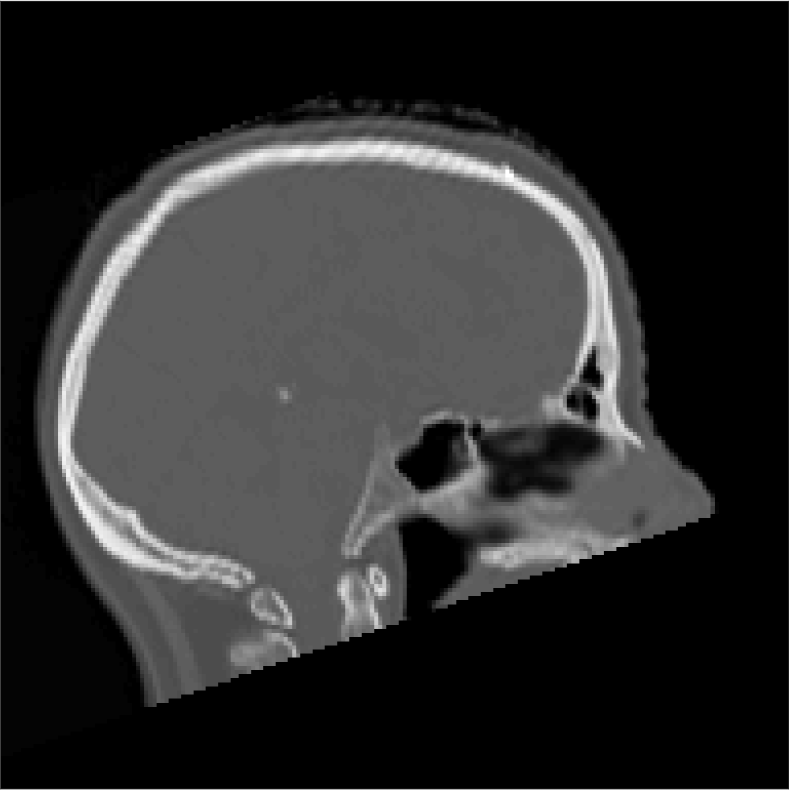

All MR images were acquired with a 1.5 T Siemens Espree scanner. The UTE images were reconstructed to 192×192×192192192192192\times 192\times 192 voxel bitmapped images with an isotropic resolution and a voxel size of 1.33 mm. The UTE sequences sampled the k-space radially with 30 000 radial spokes. CT images were acquired with a tube voltage of between 120 kV and 130 kV on either a GE Lightspeed Plus, Siemens Emotion 6 or GE Discovery 690. The in-plane pixel size varied between 0.48 mm to 1.36 mm and the slice thickness between 2.5 mm and 3.75 mm. Images of the same patient were co-registered and resampled to achieve voxel-wise correspondence between all five modes. A binary mask excluding most of the air surrounding the head was computed from the images and used to remove unnecessary data. Furthermore, to reduce the execution time of the parameter estimation phase, only 11 slices in the middle of the head of each patient was used during the parameter estimation phase, but all slices were used during the prediction phase (s-CT generation). Additional details concerning the data can be found in Johansson et al. [16]. Data from one slice of a patient is shown in Figure 3.

Refer to caption

(a) Binary mask

(b) CT

(c) First echo, 10superscript1010^{\circ}

(d) Second echo, 10superscript1010^{\circ}

(e) First echo, 30superscript3030^{\circ}

(f) Second echo, 30superscript3030^{\circ}

Figure 3: Binary data mask (panel a), CT image (panel b), The four MRI UTE sequences (panels c-f).